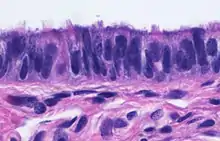

Micrograph of ciliated columnar epithelium of the fallopian tube

When viewed under the microscope, the fallopian tube has three layers.[6] From outer to inner, these are the serosa, muscularis mucosae, and the mucosa.[15][16]

The outermost covering layer of serous membrane is known as the serosa.[6] The serosa is derived from the visceral peritoneum.[14]

The muscularis mucosae consists of an outer ring of smooth muscle arranged longitudinally, and a thick inner circular ring of smooth muscle.[6] This layer is responsible for the rhythmic peristaltic contractions of the fallopian tubes, that with the cilia move the egg cell towards the uterus.[14]

The innermost mucosa is made up of a layer of luminal epithelium, and an underlying thin layer of loose connective tissue the lamina propria.[16] There are three different cell types in the epithelium. Around 25% of the cells are ciliated columnar cells; around 60% are secretory cells, and the rest are peg cells thought to be a secretory cell variant.[4] The ciliated cells are most numerous in the infundibulum, and the ampulla. Estrogen increases the formation of cilia on these cells. Peg cells are shorter, have surface microvilli, and are located between the other epithelial cells.[6] The presence of immune cells in the mucosa has also been reported with the main type being CD8+ T-cells. Other cells found are B lymphocytes, macrophages, NK cells, and dendritic cells.[16]

The histological features of tube vary along its length. The mucosa of the ampulla contains an extensive array of complex folds, whereas the relatively narrow isthmus has a thick muscular coat and simple mucosal folds.[14]